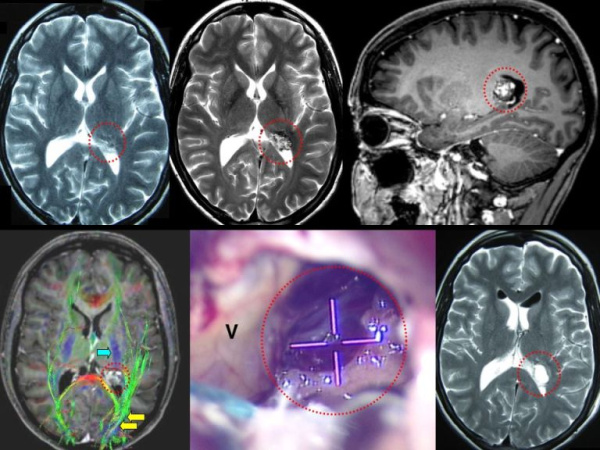

Кавернома головного мозга

Кавернома головного мозга — это церебральная сосудистая мальформация, состоящая из заполненных кровью полостей. Клинически проявляется менее чем в половине случаев. Основные симптомы включают цефалгию, судорожные пароксизмы, кровоизлияния в головной мозг. Диагностика осуществляется с применением электроэнцефалографии, церебральной МРТ, ангиографии. Консервативное лечение проводится с назначением противосудорожным препаратов. Хирургическая тактика заключается в полном иссечении каверномы. При глубинном расположении мальформации возможно использование радиохирургии или лазерной облитерации.

Согласно классификации сосудистых мальформаций, кавернома относится к кавернозной форме гемангиом. Ранее была отнесена к новообразованиям. В настоящее время считается аномалией развития сосудов. На долю каверномы головного мозга приходится около 10-15% всех мальформаций сосудов ЦНС. Более 70% имеют супратенториальную локализацию. Распространенность каверном среди населения не превышает 0,5%. Клинически проявленные случаи заболевания наблюдается у 40-45% пациентов, остальные являются бессимптомными носителями аномалии. Выявляемость патологии значительно улучшилась с внедрением в медицинскую практику методов нейровизуализации.

Диагностика

Асимптомная кавернома головного мозга диагностируется врачом-неврологом при прохождении МРТ по поводу другого заболевания или в связи с наличием диагноза у родственника. При симптомном течении в неврологическом статусе возможно выявление очаговых расстройств, нарушений речи и координации. Среди инструментальных методов исследования для диагностики каверном в современной неврологии применяются:

- КТ головного мозга. Диагностирует наличие объемного округлого образования с четкими границами. Неоднородность структуры свидетельствует о наличие петрификатов в стенках каверн. Позволяет диагностировать гематому, субарахноидальное кровоизлияние. Малоинформативно в отношении каверном среднего и малого размера.

- МРТ головного мозга. Наиболее информативный метод диагностики каверномы. Визуализирует мальформацию с 98% специфичностью. На снимках наблюдается наличие гетерогенного образования с четкими контурами с типичным ободком сигнала низкой интенсивности в режиме Т2 за счет отложений гемосидерина.

- Ангиография. В большинстве случаев не фиксирует патологические изменения. Иногда визуализирует каверному как бессосудистую область. Ангиография применяется для исключения артериовенозной мальформации, сосудистой опухоли, аневризмы.

- Гистологическое исследование. Проводится на материале, полученном при проведении операции. Выявляет наличие характерных полостей, в ряде случаев — кальцификацию, кровоизлияния. Позволяет точно верифицировать морфологический тип мальформации.